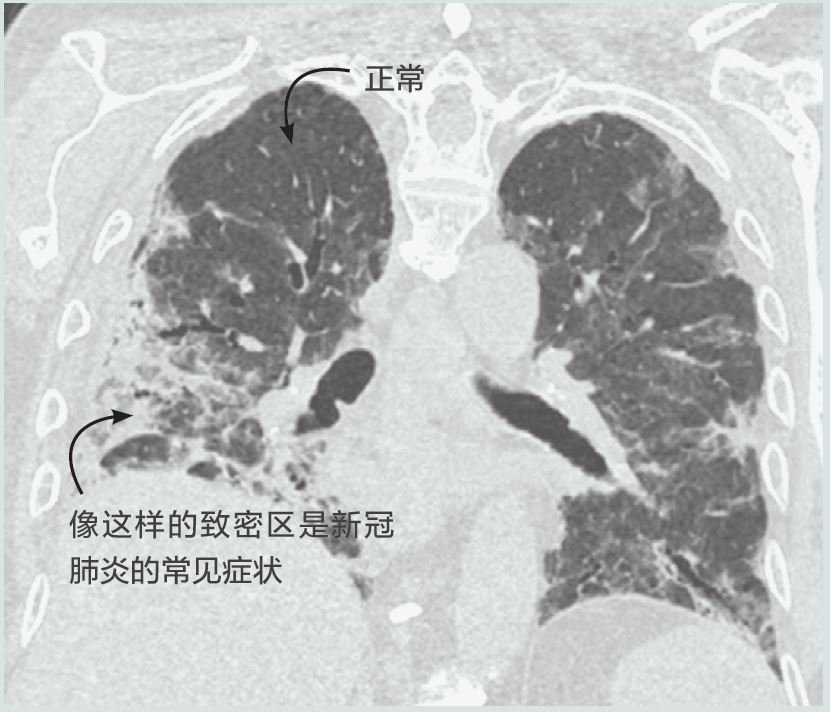

imagining-chinese-2.jpg

新冠肺炎患者的胸部CT。兩個肺都受到影響,尤其是右肺。(圖/博洛尼亞大學醫院管理局圣奧爾索拉-馬爾皮吉綜合醫院核醫學科L. Zanoni)

計算機斷層掃描(CT)是一組多重X射線成像。CT機圍繞著患者旋轉,從多個角度快速發送X射線穿過身體。在人體周圍有一個由數百個專用探測器組成的環跟蹤X射線圖案。然后由CT機強大的計算機進行處理,生成由最薄可達0.3毫米切片寬度構成的詳細圖像(通常為3D圖像)。對于評估新冠肺炎時通常掃描的身體部位即胸部的CT掃描,會生成數百張圖像來覆蓋整個胸部區域。

CT機較X光機更復雜、更昂貴,而且不像X光機那樣廣泛使用。它們也更難去污,可能需要20多分鐘,Pellet說,“CT掃描可以提供高度詳細的信息,為了做到這一點,它們比X光機使用更多的射線。因此,它們只應在適合患者的情況下使用。”